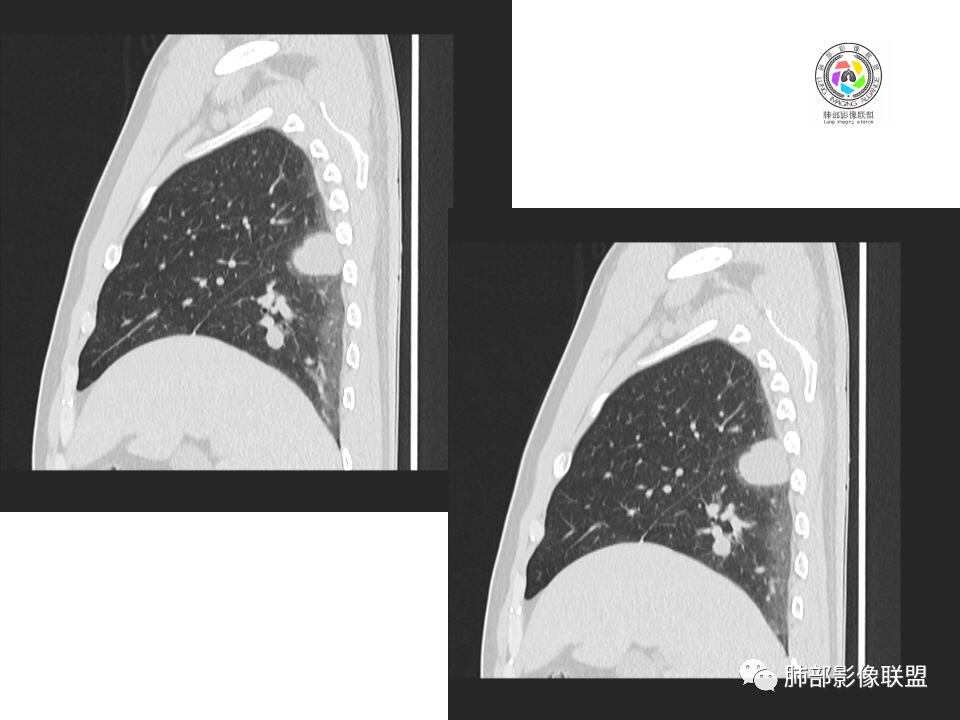

2.右肺下叶背段胸膜下块影,边界清楚光整,上下极见磨玻璃晕,未见明显分叶毛刺和棘状突起,未见胸膜凹陷或胸壁侵入。密度均匀,轻度不均匀强化。未见支气管进入。

3.右肺中叶外侧段胸膜下散在小片影,磨玻璃密度为主,边界不清,支气管相关。符合炎性特征!

4.右肺下叶基底段支气管血管束旁小结节影,边界清楚,强化不明显。注意,这结节在“遥远的”基底段。

显然本例焦点在于背段那个边缘光整的块影!